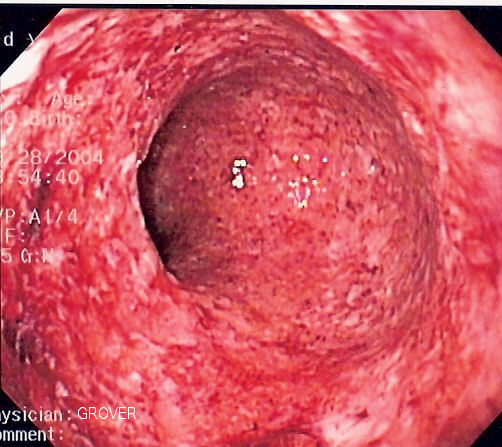

Bloody Stools

The presence of blood in the stool is a hallmark symptom of ulcerative colitis. This occurs because inflammation in the colon’s lining causes ulcers to form, and these ulcers may bleed. The amount of blood is variable; some people notice only small streaks of red, while others experience more significant bleeding. Because ongoing blood loss may lead to other health issues like anemia, individuals who notice this symptom may seek medical evaluation.